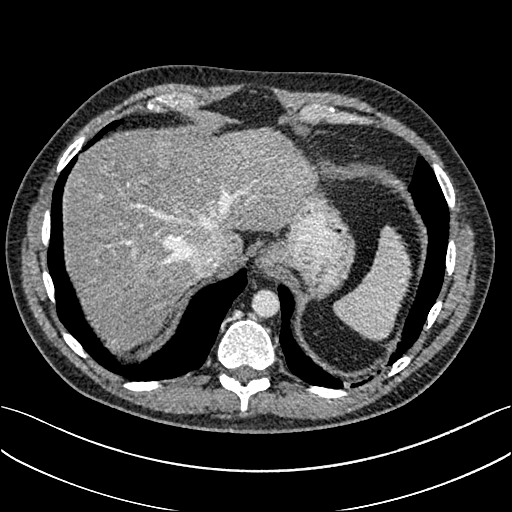

To demonstrate the effectiveness of the proposed network, we perform the qualitative comparisons over three representative abdominal images presented in Figs. 3, 5 and 7. For better evaluations of the image quality with different denoising models, zoomed regions-of-interest (ROIs) are marked by red rectangles and shown in Figs. 4, 6 and 8 respectively. Note that all results from different denoising models focus on two aspects: content restoration and noise-reduction. All CT images in axial view are displayed in the angiography window [-160, 240]HU.

The real NDCT images and corresponding LDCT images are presented in Figs. 3a and 3b. As observed, there are distinctions between ground truth (NDCT) images and LDCT images. Figs. 3a and 7a show the lesions/metastasis. Fig. 5a presents focal fatty sparing/focal fat. In Figs. 4a, 6a and 8a, these lesions can be clearly observed in NDCT images; in contrast, from Figs. 4b, 6b, and 8b, it can be seen that the original LDCT image is noisy, and lacks structural features for task-based clinical diagnosis. All adopted denoising models suppress noise to some extent.